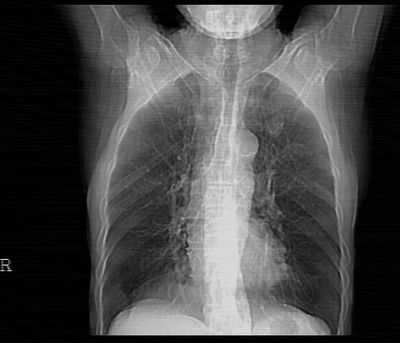

标题: CT24783:m71,既往肺心病史3年,现咳嗽,憋喘。 [打印本页]

标题: CT24783:m71,既往肺心病史3年,现咳嗽,憋喘。